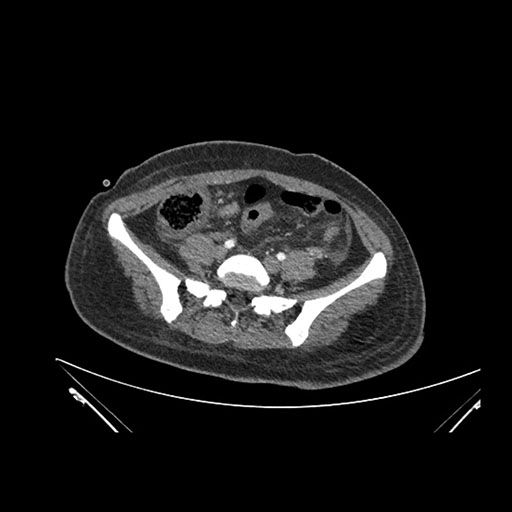

Axial Arterial